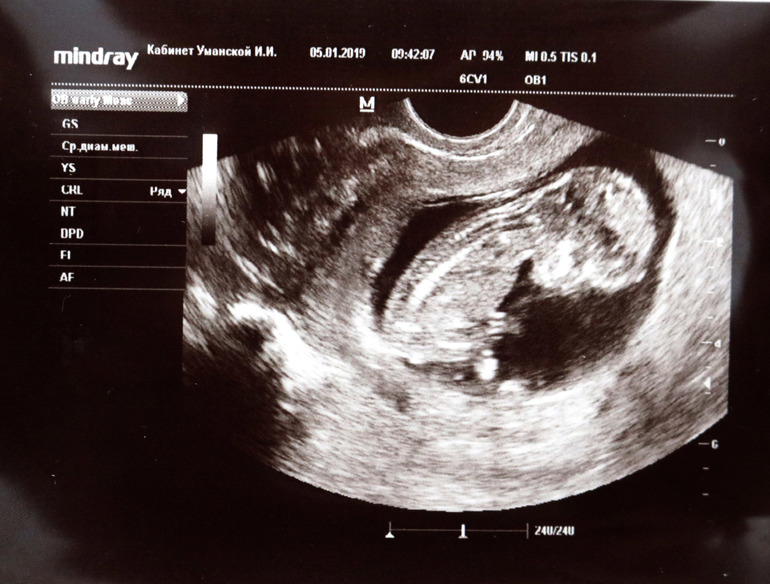

Предположили нам мальчика на УЗИ, второго сына тоже на 12 неделях обнаружили. Я так и думала ,что мальчик, но все так хотели девочку... не ждать уже, настраивать всех на мальчишечку?)) Или может еще быть надежда на то, что ошибка УЗИ? Может мой мальчик превратиться в девочку?))

Мне кажется, что на фото не видно толком ничего...

По этому фото судить точно нельзя) Если есть другое, покажи, я уже много видела мальчиков и девочек в 12 недель ))) А какой КТР, сердцебиение?